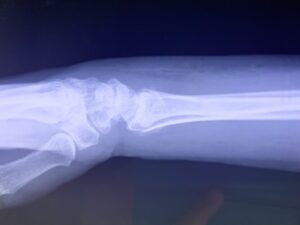

骨折・脱臼に関する研修会の役員をしています。同じ役員の先生方と講師のもと、同業の先生達に向けて骨折・脱臼の治し方の実技指導をしております。

さわやか千葉県民プラザ(上腕骨顆上骨折)

さわやか千葉県民プラザ(前腕骨下端部骨折)

春日部市市民活動センター(肘関節脱臼)

春日部市市民活動センター(上腕骨顆上骨折)

小児上腕骨外顆回転骨折の1症例について

肘関節前方脱臼の1症例について